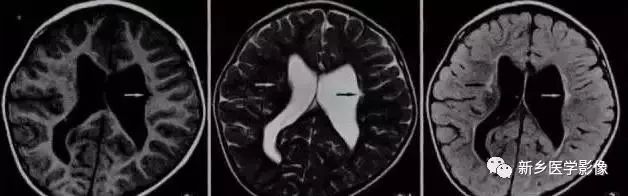

❺ 脑室周围白质软化症

主要与缺血缺氧及感染有关。常见于早产儿,是造成早产儿脑瘫的主要原因。

由于脑室周围白质的血供分别来自脑室区和远脑室区的终动脉,未成熟儿终动脉深穿支的侧支循环尚未建立,而胚胎晚期脑室周围白质对缺血缺氧敏感,所以,脑室周围自质软化症多见于早产儿。

由于病灶常为双侧性,故双侧侧脑室多同时扩大。脑白质内软化灶在CT扫描时表现为白质内斑片状低密度灶,MR上T1加权图呈低信号,T2加权图呈高信号。

❻ 脑室周围白质软化症

主要与缺血缺氧及感染有关。

常见于早产儿。原因与胚胎期脑部损害发生的时间有关:胚胎早中期脑损害主要引发发育畸形,晚期主要引起脑血管改变。

由于侧脑室周围有软化萎缩,故扩大的侧脑室外缘常不规则、不光整,这种不规则、不光整是本病引起脑室扩大的特。另外,本病均表现有脑白质量减少及脑白质内斑片状软化病灶,脑白质减少严重时表现为部分区域白质消失,脑皮层与脑室侧缘接近甚至相连。CT表现为斑片状低密度灶。MR T1WI上呈低信号,T2WI呈高信号。